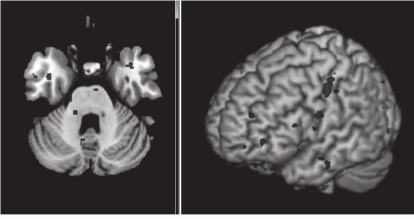

The pre-processing steps included conversion to

(Figure 2A), movement correction for unintended

head motions and spatial smoothing with 6mm

FWHM Gaussian kernel to increase signal-to-noise

Figure 2: Examples for pre-processing steps on fMRI data.

(A) Correction of individual's hemodynamic responses

slices acquired aligned to the exact same time (Sladky et

al., 2011). (B) Performance of spatial smoothing on fMRI

volume taken from single participant.